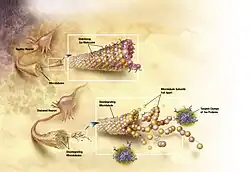

Tanto as placas amiloides como os novelos neurofibrilares são claramente observáveis ao microscópio no cérebro de pessoas com Alzheimer.[93] As placas são depósitos densos e praticamente insolúveis de peptídeos beta amiloides e material celular no exterior e em redor dos neurónios. Os novelos são agregados de proteína tau associada aos microtúbulos que se tornou hiperfosforilada e se acumulou no próprio interior das células. Embora alguns idosos possam desenvolver placas e novelos devido ao processo de envelhecimento, o cérebro de pessoas com Alzheimer apresenta um número muito superior em áreas específicas, como no lobo temporal.[94] Os corpos de Lewy não são incomuns em pessoas com Alzheimer.[95]

Bioquímica

A doença de Alzheimer é uma proteopatia, ou seja, uma doença caracterizada por anomalias no enovelamento de proteínas. É causada pela acumulação no cérebro de placas de proteínas beta amiloide e tau de enovelamento anómalo.[96] As placas são constituídas por pequenos peptídeos com 39-43 aminoácidos de comprimento, denominados beta amiloides (Aβ). Os beta amiloides são fragmentos de uma proteína maior denominada proteína precursora de amiloide (APP), uma proteína transmembranar que penetra a membrana dos neurónios. A APP é essencial para o crescimento, sobrevivência e reparação de lesões dos neurónios.[97][98] Na doença de Alzheimer existe um processo desconhecido que faz com que a APP se divida em fragmentos menores de enzima ß através de proteólise.[99] Um destes fragmentos dá origem a fibrilos de beta amiloide, que formam grupos que se depositam no exterior dos neurónios em formações densas conhecidas como placas senis.[93][100]

A doença de Alzheimer também é considerada uma taupatia devido à agregação anormal de proteína tau. Cada neurónio tem um citoesqueleto, uma estrutura interna de suporte constituída parcialmente por estruturas denominadas microtúbulos. Estes microtúbulos atuam como carris, orientando os nutrientes e as moléculas do corpo das células para as extremidades dos axónios e vice-versa. A proteína tau estabiliza os microtúbulos quando fosforilada, pelo que é denominada proteína associada aos microtúbulos. Na doença de Alzheimer, a proteína tau sofre alterações químicas, tornando-se hiperfosforilada, e começa a associar-se com outros novelos, cria novelos neurofibrilares e desintegra o sistema de transporte dos neurónios.[101]